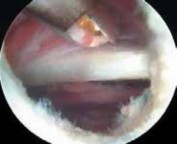

TECHNIQUES A B C D E F G H I ### FIG 4 • A–G. The iliopsoas tendon of the right hip is exposed from the peripheral compartment. A. The initial tendon viewed through a capsular window is fully identified, but is abnormally small. B. This tendon is released with a basket. C. A stump remains. D. This is resected with a shaver. E. Further dissection exposes a more substantial portion of the iliopsoas tendon. F. This is released as well. G. Complete release of the bifid tendon is documented. H,I. Viewing the iliopsoas tendon of a right hip at its insertion on the lesser trochanter within the iliopsoas bursa. H. A bifid iliopsoas tendon is identified with medial (

) and lateral () bands separated by a vessel (

two white asterisks

) coursing perpendicular. I. The lateral band (

black asterisks

) has been released with a flexible RF device, revealing the medial band (

white asterisk

) which subsequently is released. (Courtesy of J. W. Thomas Byrd, MD.)**